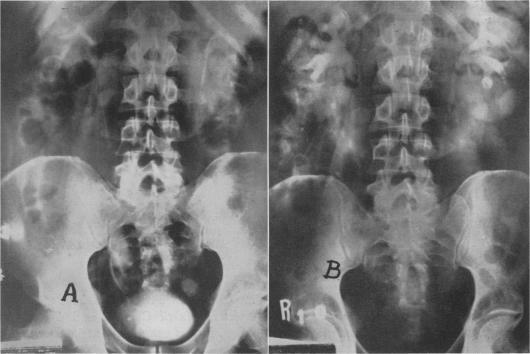

Ureterosigmoidostomy; experience with the Goodwin procedure.

Ann Surg. 1956 Mar;143(3):337-48. doi: 10.1097/00000658-195603000-00006.